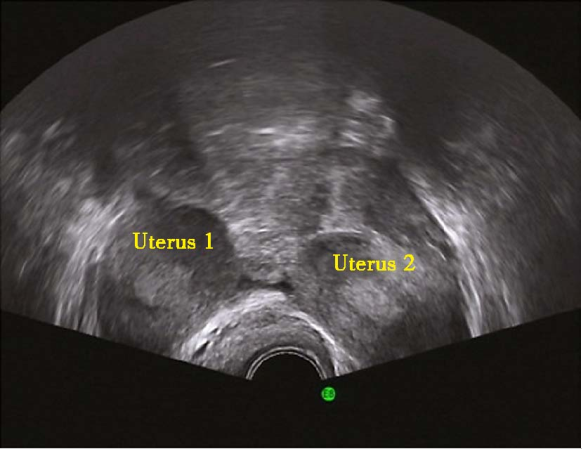

双子宫二维超声

双子宫三维超声

(四)双子宫(didelphid uterus)

为两侧副中肾管未融合,各自发育形成两个子宫和两个宫颈,也可为一侧子宫颈发育不良、缺如。双子宫可伴有阴道纵隔或斜隔。患者多无自觉症状。伴有阴道纵隔者可有相应症状。检查可扪及子宫呈分叉状。宫腔探查或子宫输卵管碘油造影可见两个宫腔。一般不予处理。当有反复流产,应除外染色体、黄体功能以及免疫等因素后行矫形手术。